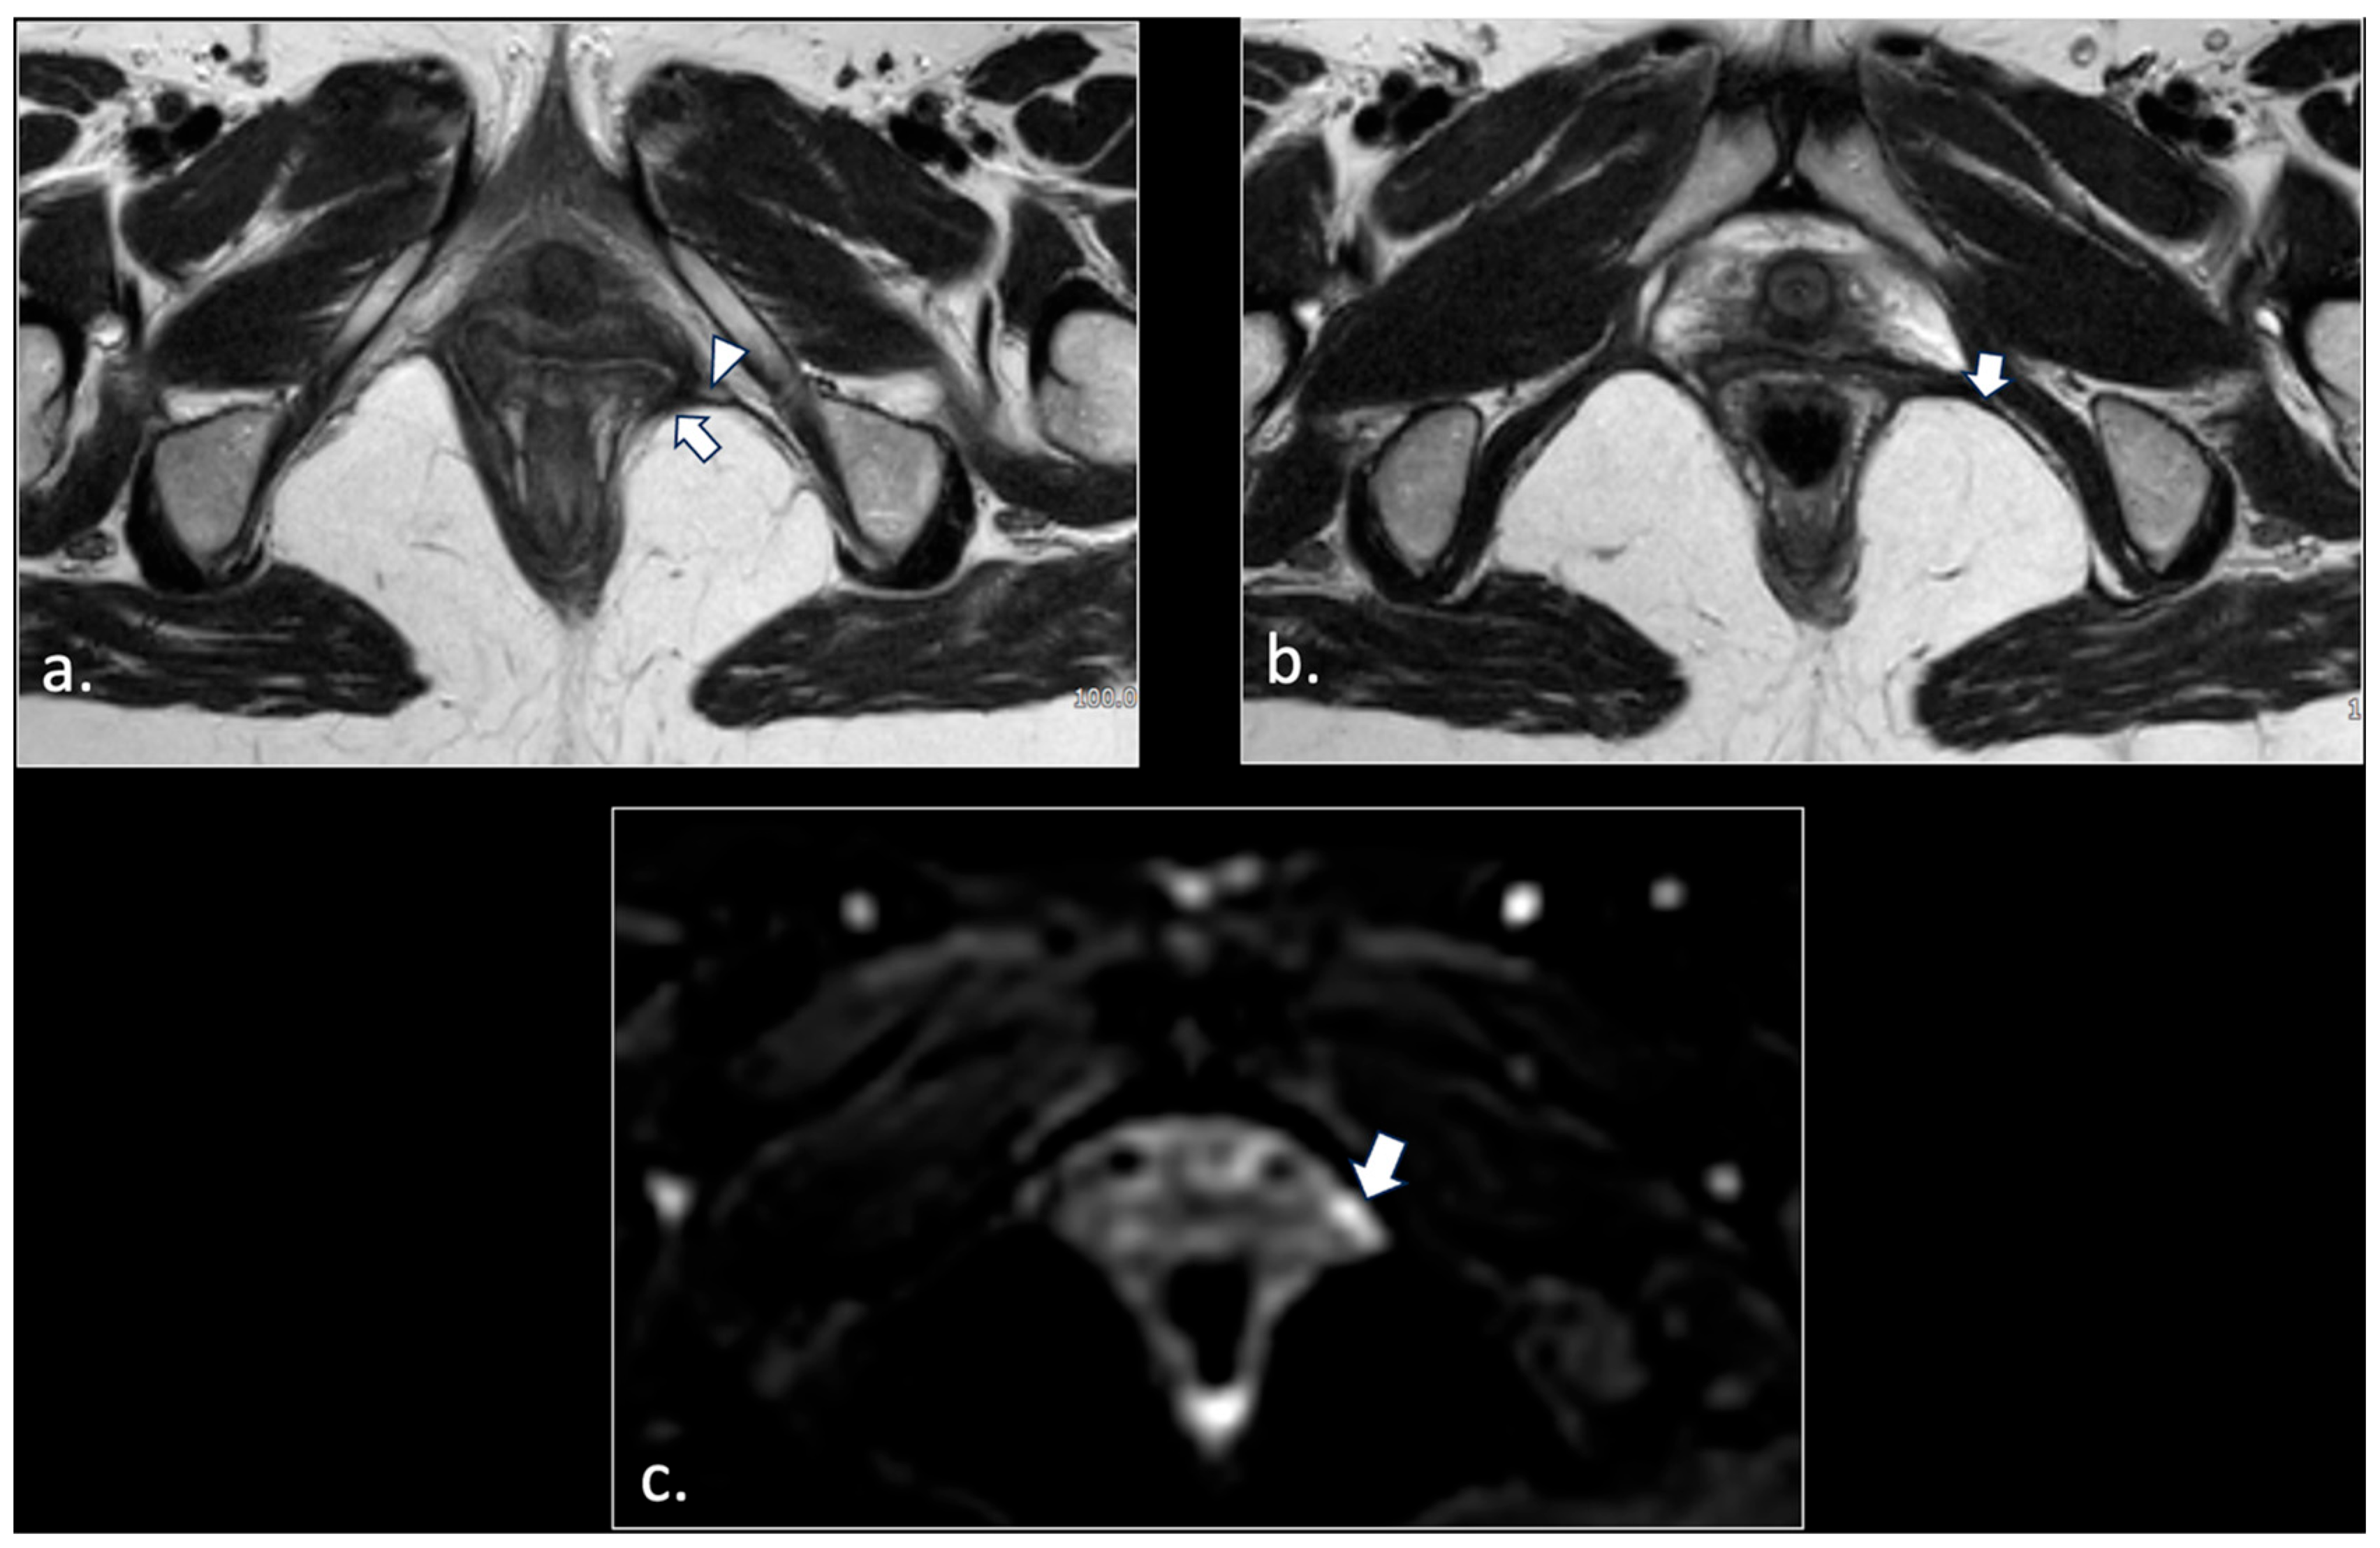

- Hemorrhagic Tarlov’s cyst of the sacrum (1 patient);

- Unilateral rupture of puborectal and/or pubococcygeal muscle (4 patients);